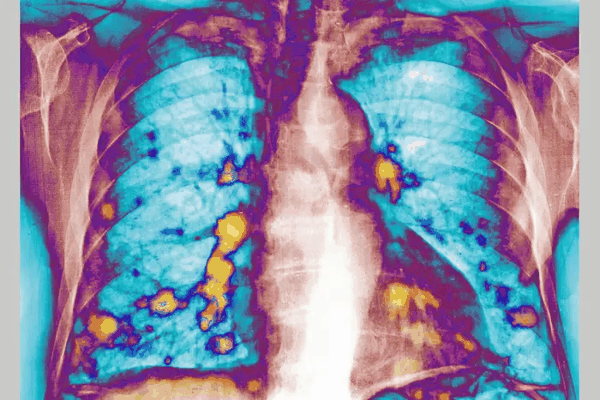

肺部是癌症从身体其他部位最常扩散到的部位之一。图源:CAVALLINI JAMES

肺部是癌症最常见的扩散部位之一。对小鼠进行的实验表明,RSV似乎能够触发一种免疫反应,暂时使源于乳腺的癌细胞更难扩散到肺部。